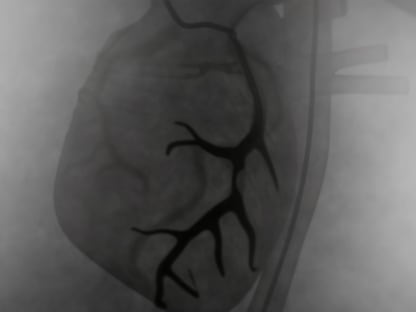

- Coronary angiogram. This is an invasive test to look at blood flow in the coronary arteries.